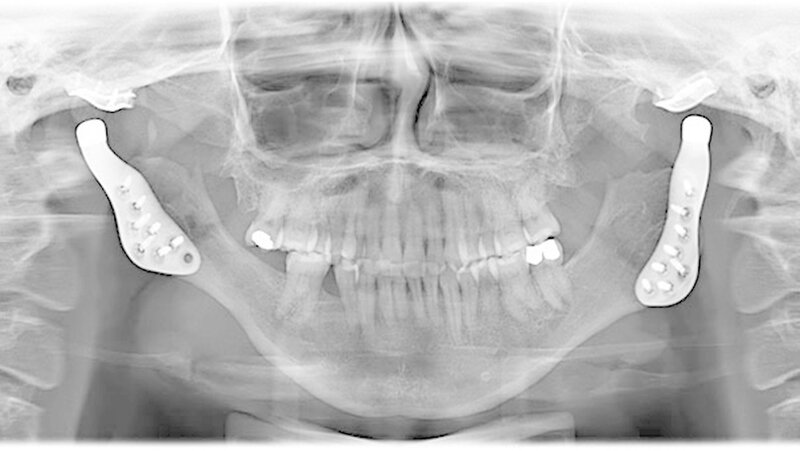

Das Bonner MKG-Chirurgenteam um Prof. Dr. Dr. Rudolf Reich diagnostizierte eine zunehmende Einschmelzung (Resorption) der Kiefergelenkfortsätze, wodurch die gesamte Abstützung des Unterkiefers am Schädel verloren gegangen war.

Da in diesen Fällen eine sichere Wiederherstellung der Abstützung des Unterkiefers mit eigenem Gewebe wie beispielsweise Knochen nicht möglich ist, weil eine erneute Einschmelzung droht, hat sich der Kiefergelenkersatz mit Endoprothesen bewährt.

Therapie: Kiefergelenkersatz mit Endoprothesen

Mit der virtuellen Planung, individuellen Kiefergelenkprothesen und einer zusätzlichen Rückpositionierung des Oberkiefers in die ursprüngliche Lage erfolgte dann die Operation. Alles erfolgte in einem Operationsgang. Die Bonner MKG-Chirurgen fertigten die Endoprothesen für die Frau individuell im CAD-/CAM-Verfahren an. Dafür wurden die Daten der Computertomografie des Schädels zugrunde gelegt.